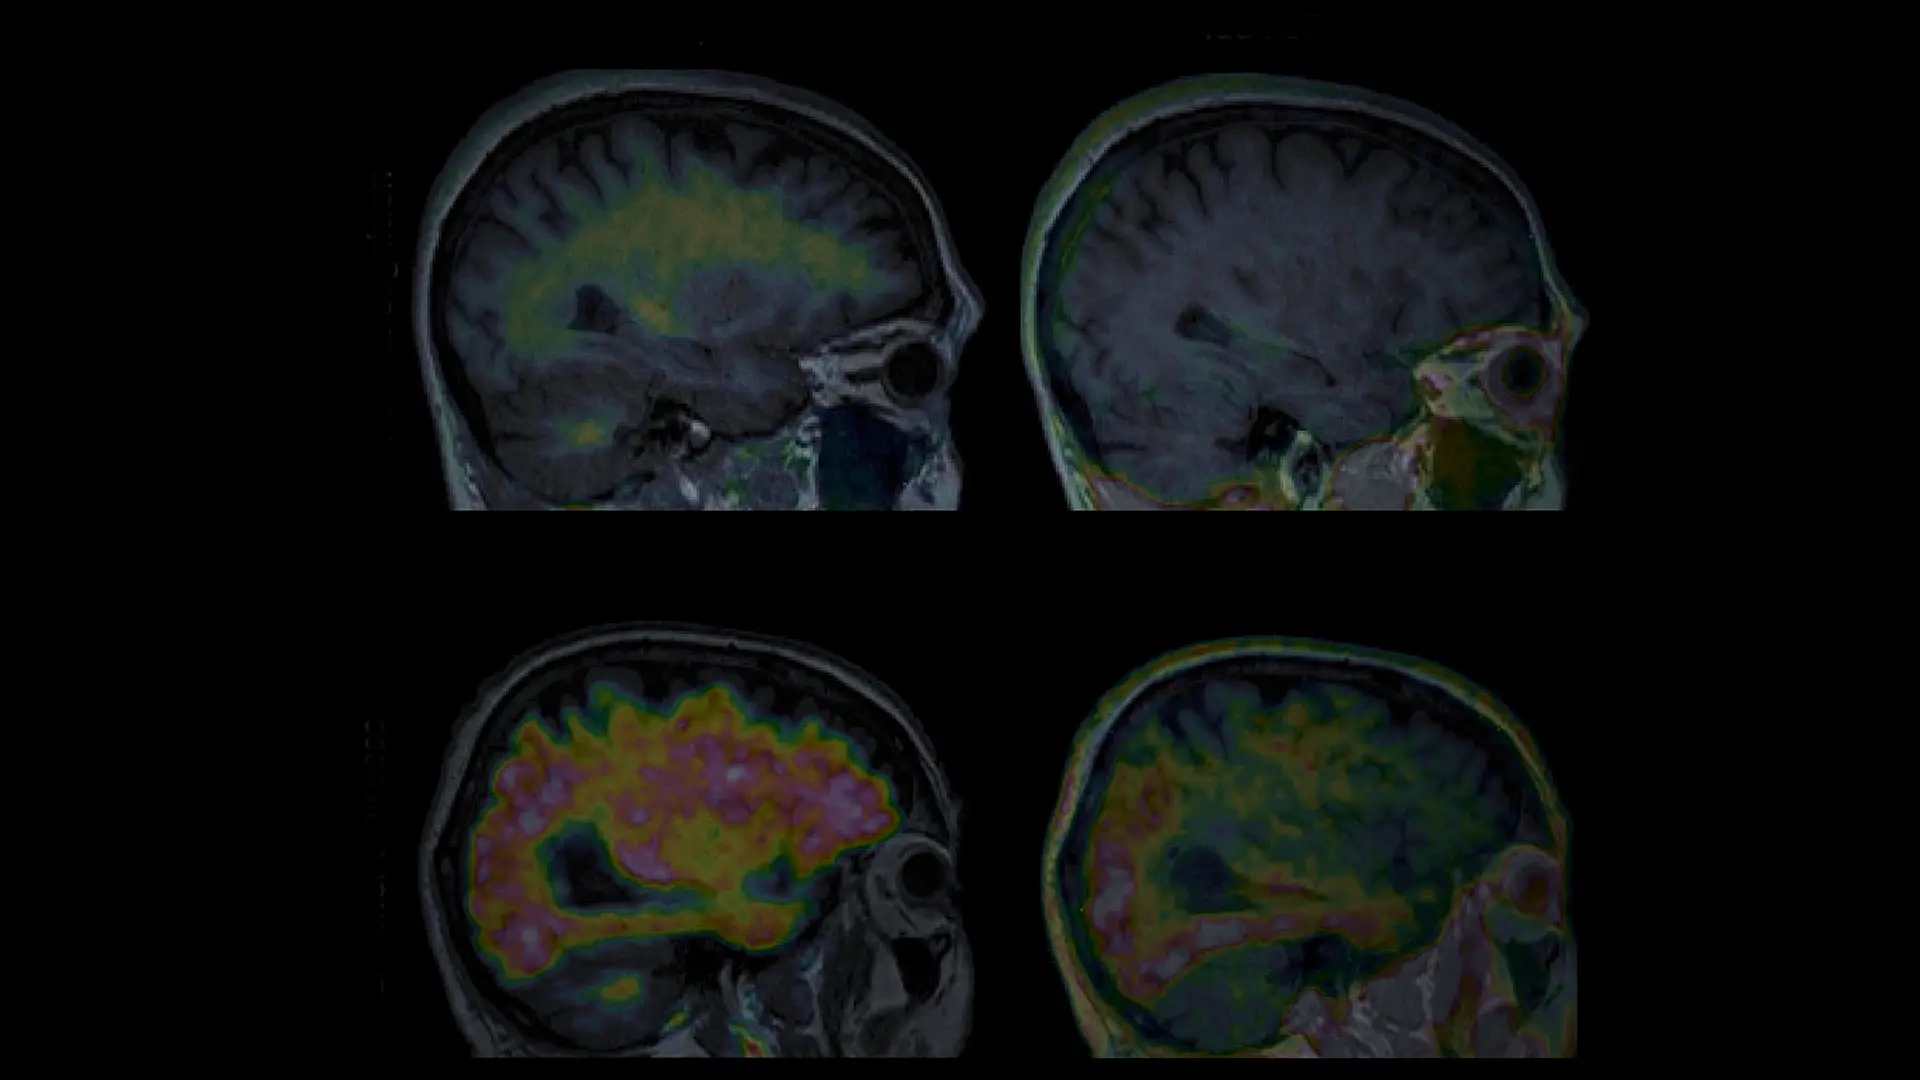

Figure 1. Amyloid and tau PET images from an older individual with normal cognition, and from a patient with AD.

Research now shows that much of what has been considered to be age-related memory loss may actually reflect undiagnosed AD. Individuals with amyloid plaques exhibit memory test declines years before diagnosis of mild cognitive impairment. Those with both amyloid and tau exhibit even more rapid memory decline. Recently developed blood tests can detect tau fragments, offering a less invasive way to indicate AD pathology. In collaboration with physician-scientist Fanny Elahi, MD, PhD, Dr. Hedden is evaluating how such blood assays can guide decisions about whether PET imaging should be performed. As these tools become more available, AD may be detected at its onset—and perhaps treated before memory decline appears.

Anti-amyloid therapies can remove plaques, though their benefit for memory preservation remains modest and risks can be significant. Tau-targeting therapies are also in development, raising hope that early detection combined with intervention may one day prevent memory loss from AD altogether.